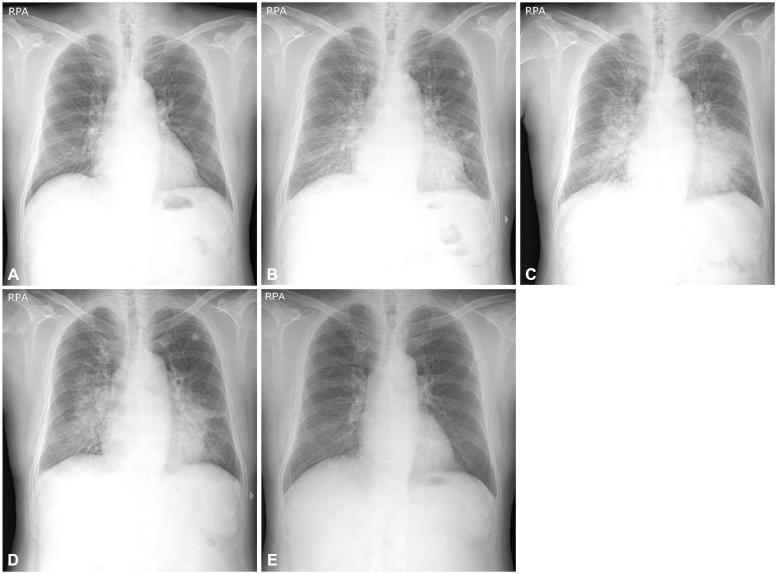

Non-cardiogenic pulmonary edema (NCPE) is a rare adverse reaction to iodinated radiocontrast media (RCM), in which all previous cases were immediate reactions. A 56-year-old male was given iopamidol, a non-ionic, low osmolar RCM, during coronary artery angiography. He developed pulmonary edema and fever a day after the procedure. Despite diuretic therapy, the patient's pulmonary edema worsened and his high fever persisted. The patient's pulmonary edema was eventually resolved with intravenous steroid treatment. We interpreted the patient's condition as NCPE manifesting as a delayed reaction to RCM. To our knowledge, our case is the first to show NCPE as a delayed hypersensitivity reaction.

非心源性肺水肿(NCPE)是碘造影剂(RCM)罕见的不良反应,此前所有病例均为即刻反应。一名 56 岁男性在冠状动脉造影期间使用了一种非离子型、低渗的 RCM 碘帕醇。在操作后一天,他出现肺水肿和发热。尽管给予利尿剂治疗,但患者的肺水肿仍恶化,高热持续。患者的肺水肿最终通过静脉注射类固醇治疗得到缓解。我们将患者的病情解释为 RCM 迟发性过敏反应引起的 NCPE。据我们所知,我们的病例是首例显示 NCPE 为迟发性过敏反应的病例。